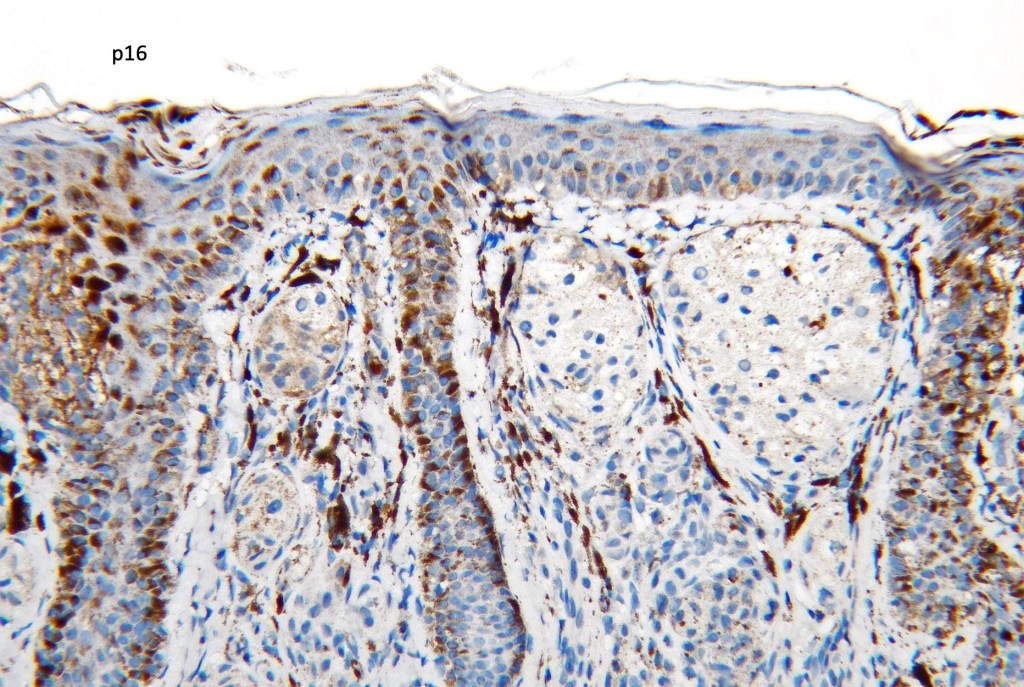

•Cells stain with HMB45, SOX10, S100, Melanoma-A